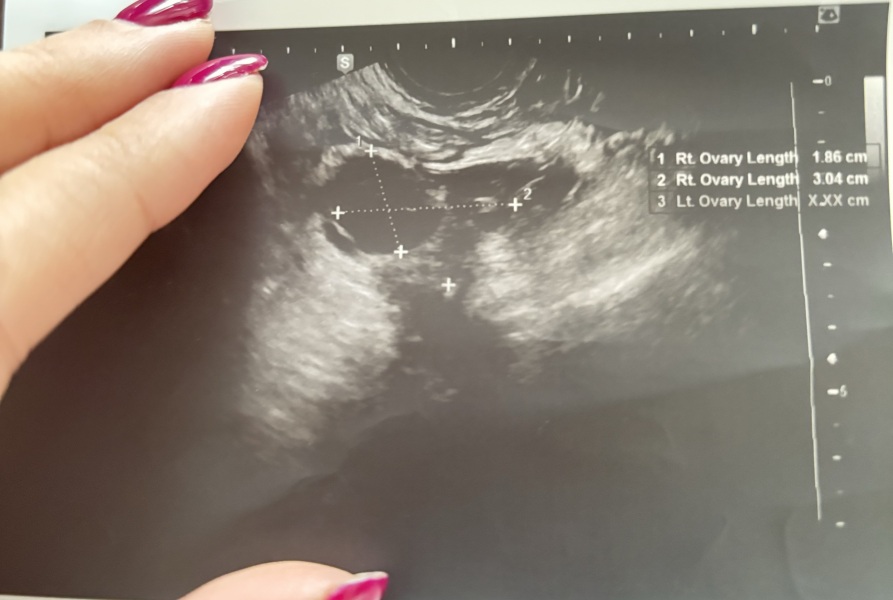

hello all, went on a follicle scan on CD 12, the doc told me that I have a dominant follicle in the left ovary, but from the image I can see there is a second dominant one next to it. Can you take a look and tell me if you see it or it is just my imagination? 🥲